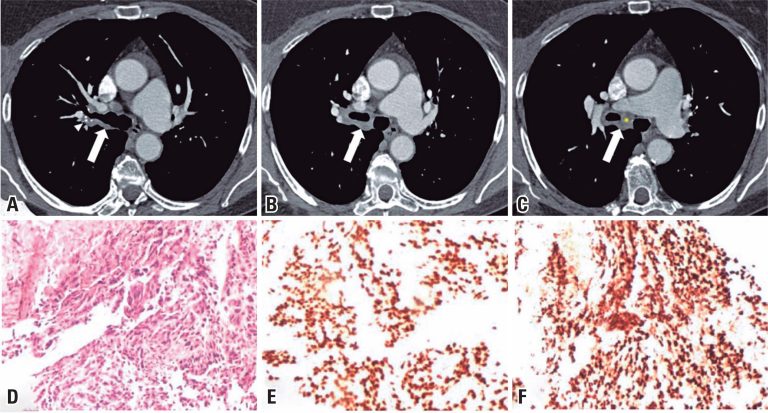

A 78-year-old non-smoking female patient presented to the medical office with a history of two self-limited episodes of hemoptysis occurring 8 weeks prior. She had previously undergone treatment for ductal adenocarcinoma in the right breast 17 years ago, involving mastectomy followed by chemotherapy and radiotherapy.

Physical examination revealed no abnormalities, and her SpO2 was 98% on room air. A CT scan exhibited circumferential thickening of the right main bronchus, encompassing the origin of the upper lobe bronchus and extending to the intermediate lobe bronchus (-). Further investigation included bronchoscopy, bronchoalveolar lavage, endobronchial biopsy, and serological tests. Immunohistochemistry results from the endobronchial biopsy revealed metastatic adenocarcinoma of the breast (-). Consequently, the patient was referred to oncology.